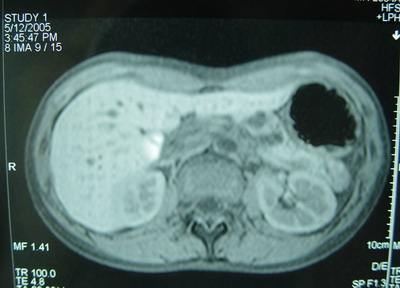

胰腺MRI